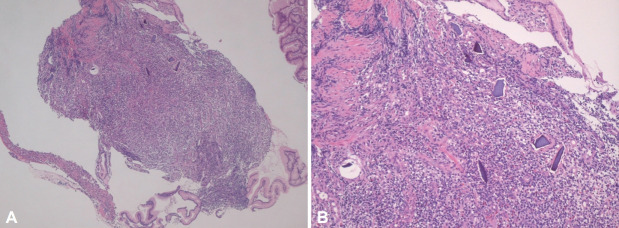

Kalimate(聚苯乙烯磺酸钙)是一种阳离子交换树脂,常用于临床治疗高钾血症。然而,Kalimate已被证明也会导致严重的胃肠道损伤,如结肠坏死、溃疡和穿孔,在慢性肾功能衰竭患者的亚群中;这些病例的报告有高渗山梨醇的管理和不。这些病变通常发生在大肠或小肠;发生在胃的病变很少被报道。我们报告了一名62岁的妇女,她患有非常大的Kalimate诱发的胃溃疡,被误诊为晚期胃癌的慢性肾衰竭患者,她已经服用了Kalimate 3个月。患者通过停用Kalimate和启动质子泵抑制剂成功治疗。

Kalimate (calcium polystyrene sulfonate) is a cation-exchange resin commonly used in clinical practice to treat hyperkalemia. However, Kalimate has been demonstrated to also cause serious gastrointestinal injuries, such as colonic necrosis, ulcerations, and perforations, in a subset of patients with chronic renal failure; these cases have been reported with and without the administration of hypertonic sorbitol. These lesions usually occur in the large or small intestine; lesions occurring in the stomach are rarely reported. We present the case of a 62-year-old woman with very large Kalimate-induced gastric ulcers that were mistaken for advanced gastric cancer in patients with chronic renal failure who had been taking Kalimate for the previous 3 months. The patient was successfully treated by discontinuing Kalimate and initiating a proton pump inhibitor.